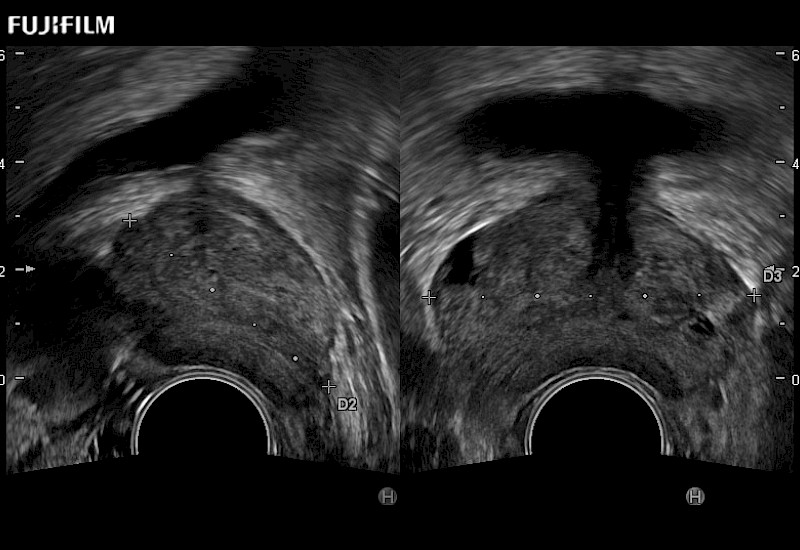

Provides real-time imaging of both the sagittal and transverse planes

Main Specifications: